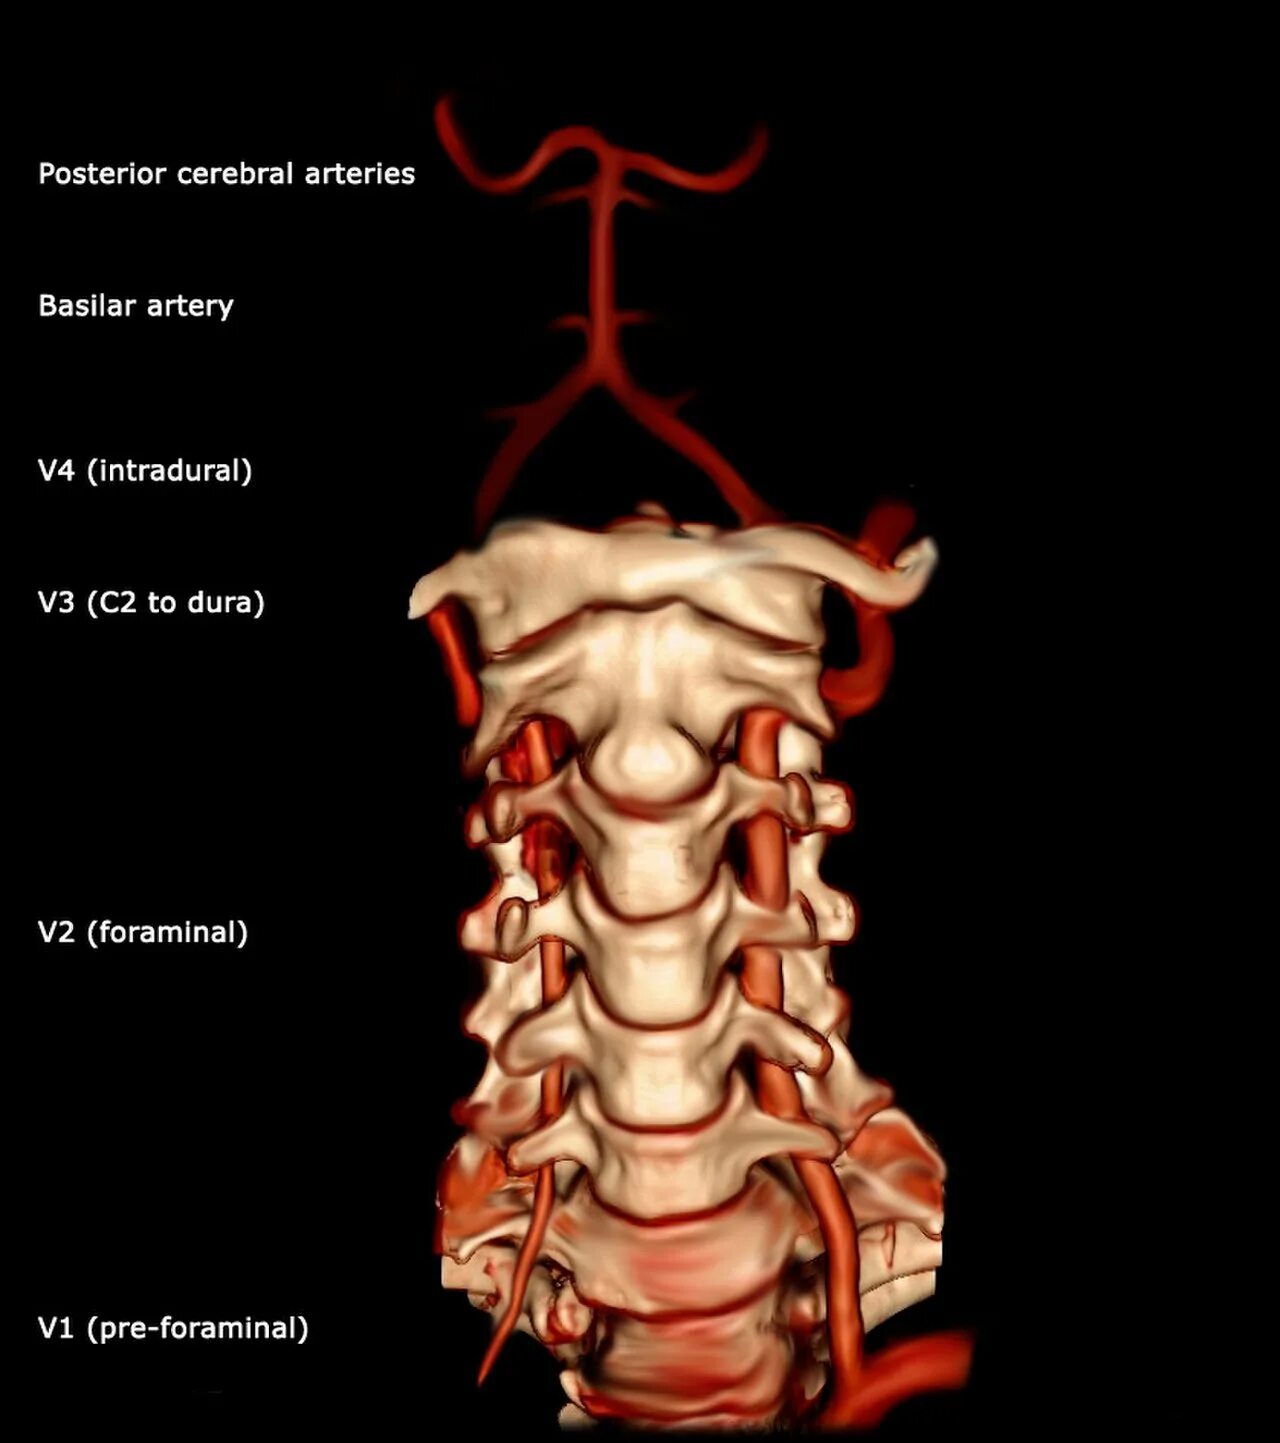

Интракраниальные сегменты